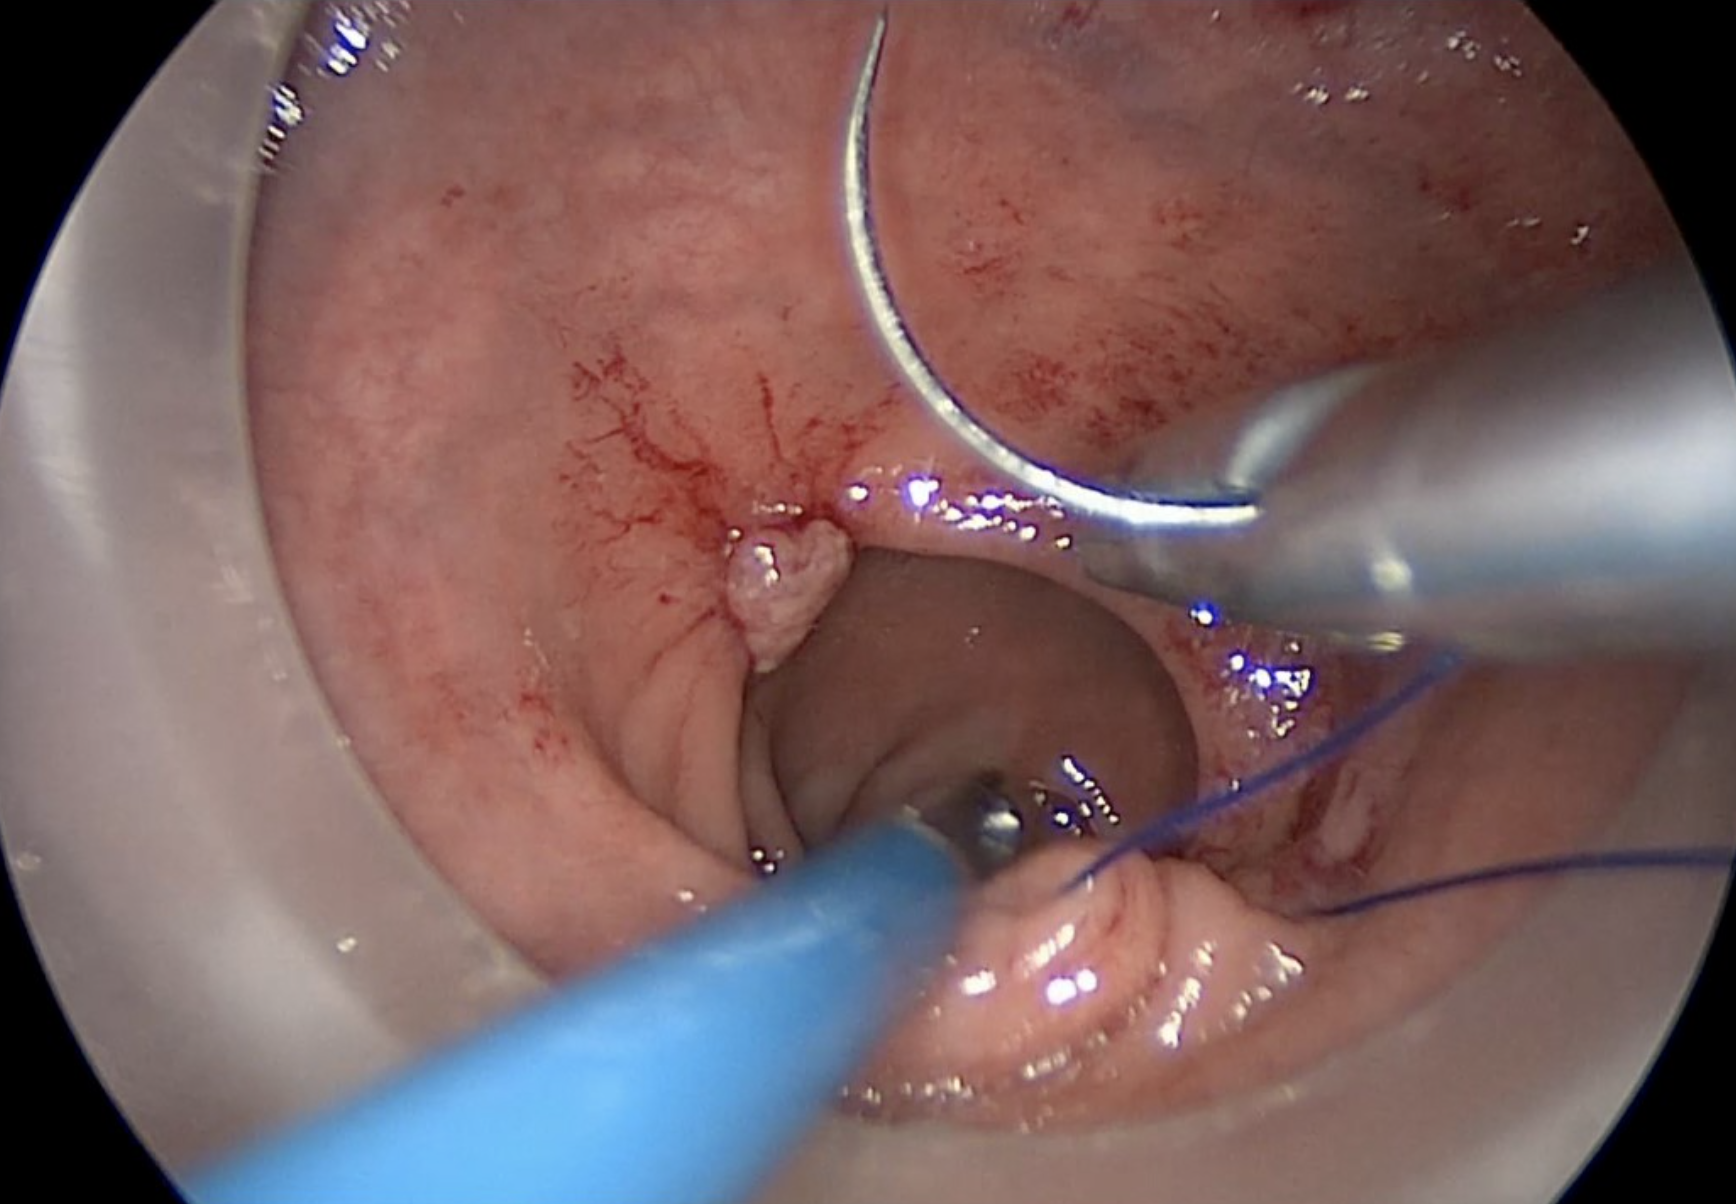

The placement of an 0 Prolene purse-string suture is the initial step of the transanal technique. It is placed from within the rectum to seal the lumen below the tumour, and to mark the distal resection margin.

Copyright Dr. Joep Knol

Placement of rectal pursestring. Note the dotted line indicating the accurate circumferential placement of the stitch below the lower edge of the tumour.